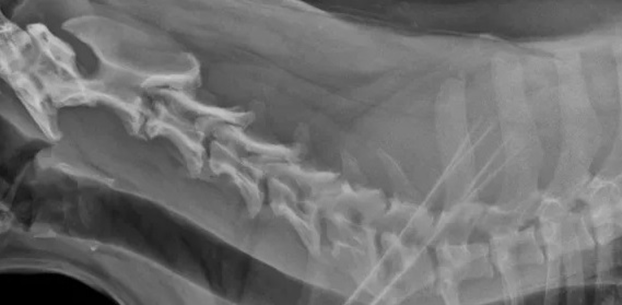

Σπονδύλωση μεταξύ των σπονδύλων Α6-Α7. Πλάγια προβολή αυχενικής μοίρας ΣΣ που απεικονίζεται πλήρης οστέινη γέφυρα μεταξύ Α6-Α7.